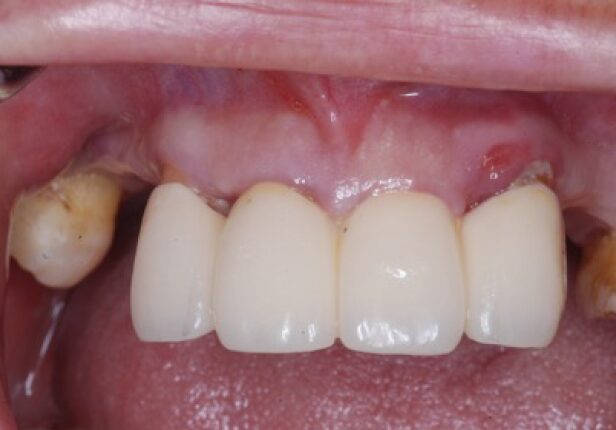

Ponte ARi caso de estudo

caso de estudo

Panorâmica pré-cirúrgica

Antes da cirúrgia

Colocação do implante

Posicionamento AXA

Scan

Contorno

Panorâmica Pós-Cirúrgia

Coroa temporária após 1 mês